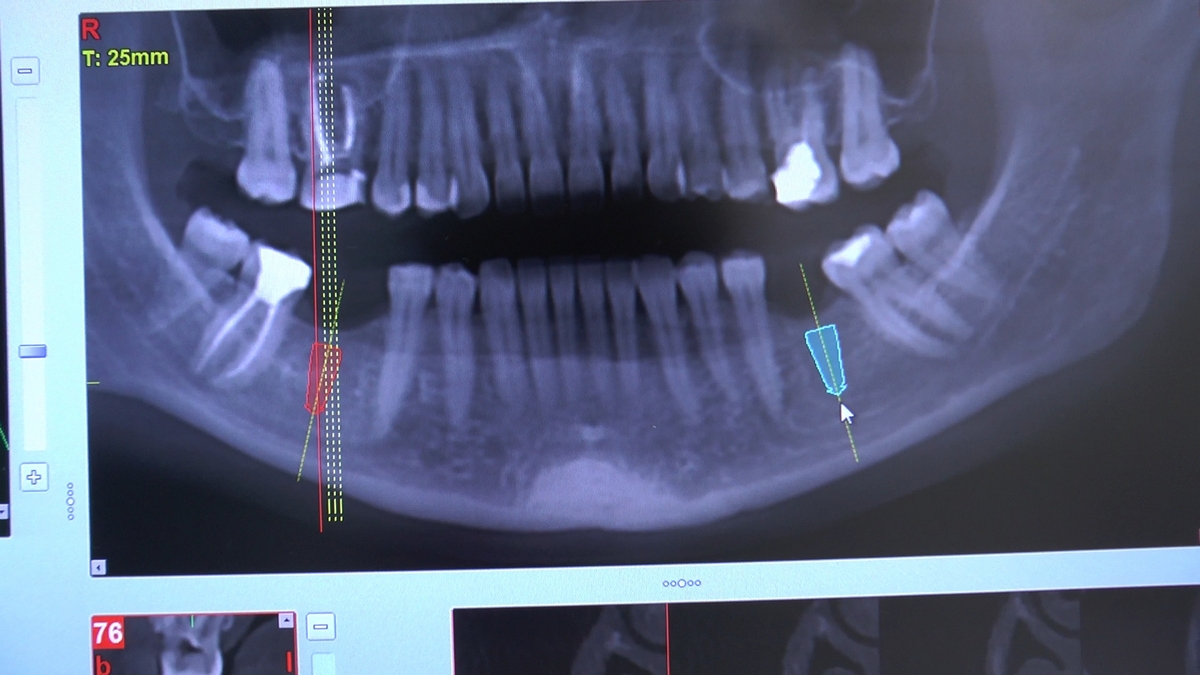

W trakcje dwóch dni zabiegowych, piątek i sobota, 5 i 6 października 2018 roku, lekarze uczestniczący w 6 Sesji VI Sezonu, wykonali wiele zabiegów o wysokim stopniu trudności. Przeprowadzili je pod kierunkiem Mentorów Instytutu Vivadental – dr n.med. Violetty Szycik, dr n.med. Magdaleny Kisłowskiej-Syryczyńskiej oraz dr Małgorzaty Piotrowskiej.

Wprowadziliśmy łącznie 25 implantów w tym wykonaliśmy:

dwa zabiegi All- on -4 / jeden w szczęce, jeden w żuchwie/ z usunięciem zębów i natychmiastową implantacją oraz natychmiastową odbudową protetyczną

jeden zabieg sinus lift otwarty

zabiegi regeneracji kości z zastosowaniem materiałów kościozastępczych i kości własnej oraz fibryny bogatopłytkowej,